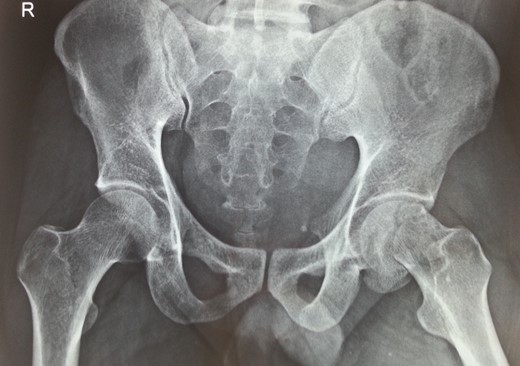

Following trauma patient had left-sided chest pain, frontal headache and severe pain in his left hip region. After hemodynamic stabilization and preliminary treatment for his chest and head injuries, he was evaluated for left hip region pain. Clinically patient had left anterior hip joint line tenderness. Initial X-ray imaging showed impacted subcapital fracture of femur neck, with varus angulation between femur head and neck (Fig. 1), which prompted detailed radiological evaluation. A 3D reconstructed CT scan imaging disclosed a separate fracture line in femur head, with a detached inferior head fragment (Fig. 2); thus, the patient had concurrent ipsilateral fracture of femur head and neck without hip dislocation. We decided to treat this fracture pattern surgically with either osteosynthesis and fixation, or primary total hip arthroplasty. Via posterolateral approach to hip, femur head and neck fractures were exposed. Proximal femur fragment showed severe impaction of cancellous bone, making chances femur head salvage with osteosynthesis precarious. Thus, we performed primary uncemented total hip arthroplasty (Fig. 3). Presently, the patient is 5 years post-surgery without any complaints and ambulates without support or limp.

CT scan image of the patient in transverse cut. Yellow arrow pointing to the subcapital fracture line of left hip and red arrow pointing to the oblique fracture line of left femur head.